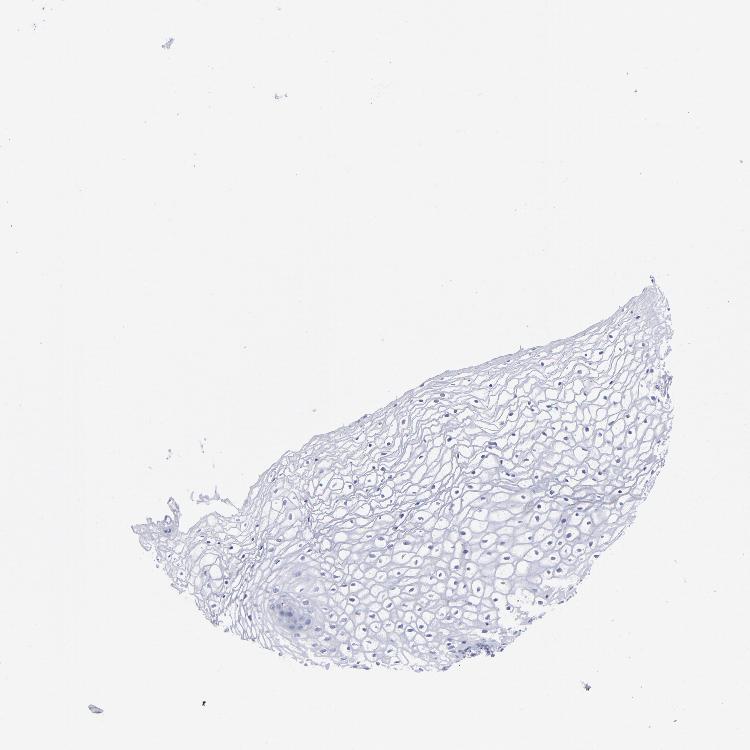

Antibody HPA003462

Squamous epithelial cells Not detected